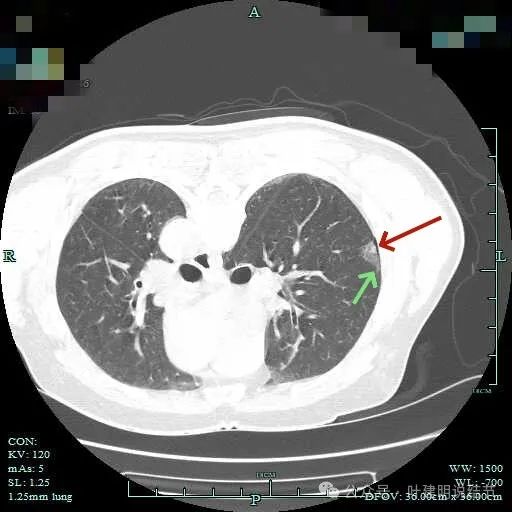

先来看两肺多发结节的总体情况:

图片

病灶1:左上叶肺尖淡磨玻璃影,轮廓稍显模糊,少许慢性炎或肺泡间隔增宽可能性大。